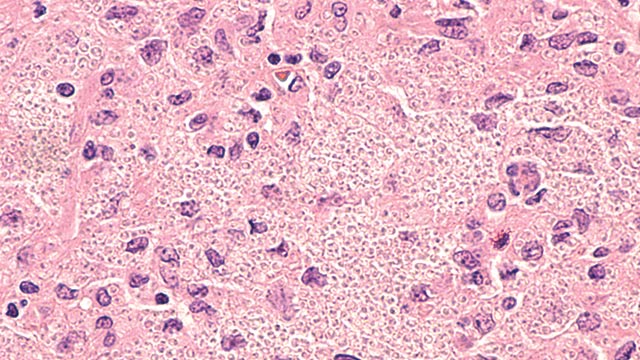

Ringworm, dermatofitosis, atau biasa disebut kurap adalah penyakit kulit infeksius yang bisa menyerang hewan dan juga manusia. Penyakit ini disebabkan oleh jamur dermatofita, salah satu spesiesnya ialah Microsporum gypseum. Spesies […]